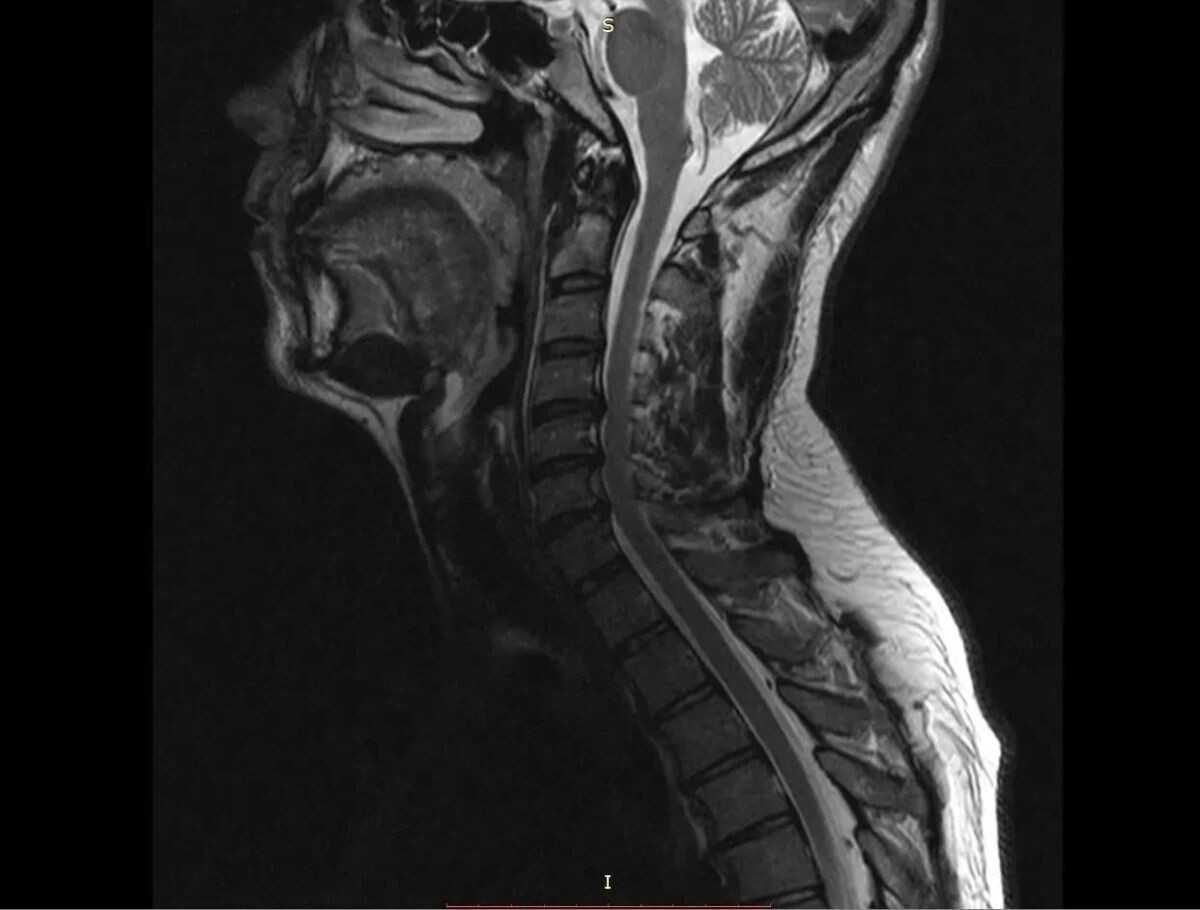

Нейрохирурги Воронежской городской клинической больницы скорой медицинской помощи №1 (БСМП №1) провели уникальную операцию 38-летнему пациенту, полностью восстановив ему свободу движений в руках. Команда под руководством заведующего отделением Павла Юрова устранила стеноз позвоночного канала, стабилизировала и укрепила шейный отдел титановыми конструкциями. Об этом сообщили в пресс-службе министерства здравоохранения Воронежской области 30 марта.

Мужчина годами мучился от остеохондроза шейного отдела. С августа 2025-го боль усилилась, распространилась на правую руку, добавив слабость и онемение. В стационаре мужчине поставили диагноз – диско-остеофитный стеноз позвоночного канала.